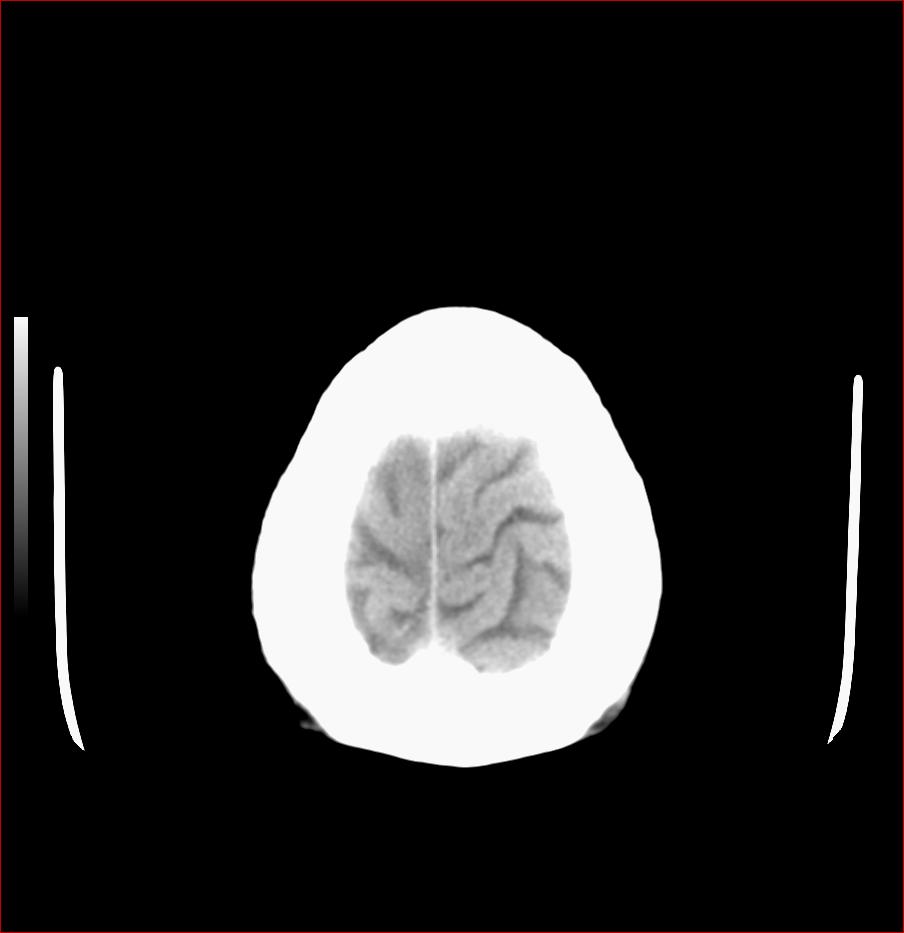

男,84岁,左下肢无力伴口角歪斜1天,血压160/80。请问一下双侧基底节区是脑梗塞吗?

基底节区脑梗塞,脑萎缩,左侧小脑脑梗塞

多发腔隙性梗死,轻度小脑萎缩。

老年性三联症_多发腔隙性梗死 脑萎缩 脱髓鞘变性.